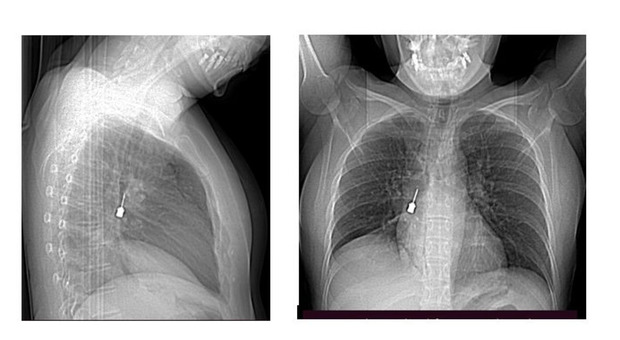

Un cacciavite odontoiatrico inalato accidentalmente e rimasto incastrato in un bronco polmonare. È la scoperta choc che ha portato una giov...